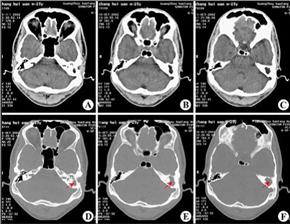

CT显示:左侧慢性中耳乳突炎(胆脂瘤型)